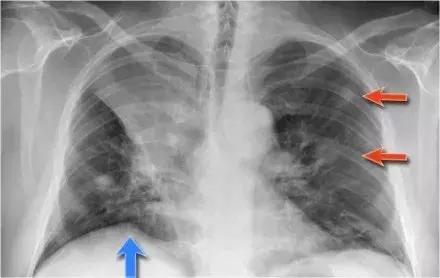

➢右上叶肺不张的常见表现是“右隔隆起”(蓝色箭头)

➢患者为右上叶中心性肺癌,伴有双肺转移(红色箭头)

图4 右上叶肺不张